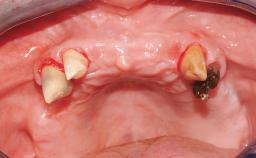

A fully edentulous 65-year-old woman was referred to our clinic for esthetic and functional dental rehabilitation. The patient presented with inadequate complete maxillary and mandibular prostheses, insufficient vertical dimension, and extensive tooth wear. The clinical examination and anamnesis showed no local or systemic contraindications, no signs or symptoms of bruxism, and an absence of smoking habits. The treatment proposed was implant placement in the mandibular interforaminal area and immediate loading with a fixed definitive prosthesis. A removable mucosa-supported complete prosthesis was indicated for the upper jaw, since its bone structure offered satisfactory retention and the financial condition of the patient disfavored a full-mouth implant-supported rehabilitation.